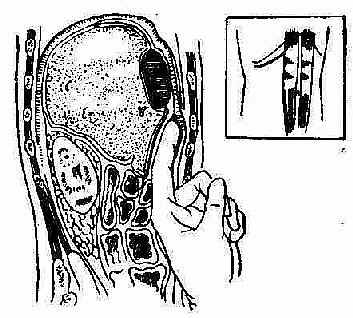

①膈下区隙(图2-39),在横结肠及其系膜之上,横膈之下及左右腹壁之间整个间隙,均称隔下间隙。膈下间隙分为肝上间隙和肝下间隙。

②肝上间隙、被冠状韧带分为右肝上间隙和左肝上间隙

③右肝上间隙、又被右侧韧带分为右肝前上间隙和右肝后上间隙。

④左肝上间隙:因左侧韧带是自横膈伸展到肝脏左叶的后面,故左肝上间隙只是一个间隙。

因此肝上间隙共分为、右前上,右后上,及左上三个间隙。

⑤肝下间隙、被镰状韧带分为左右两部分,即右肝下间隙及左肝下间隙(左肝前下及左肝后下间隙)。

图2-40 右肝前上间隙脓肿的切开引流术

插图示 皮肤切口的位置,是在右侧肋缘平行。切开腹壁肌层和横筋膜后,用手指将壁层腹膜向膈肌分离,直至脓肿的部位,即可使脓肿获得腹膜外之引流。